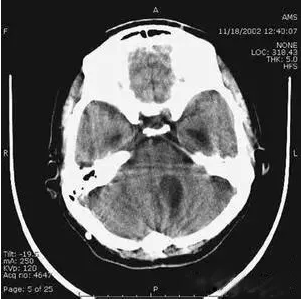

6、部分容積效應(yīng)產(chǎn)生的偽影及對策

部分容積效應(yīng)偽影的形狀可因物體的不同而不一樣,一般在重建后橫斷面圖像上可見條形、環(huán)形或大片干擾的偽像。最常見和典型的現(xiàn)象是在頭顱橫斷面時的顳部出現(xiàn)的條狀偽影,又稱哼氏偽影。該偽影現(xiàn)象可采用薄層掃描而減弱;在西門子系列的CT機中.用VAR掃描技術(shù)可抑制該偽影。

射線束硬化使X線光子吸收不均衡,相應(yīng)產(chǎn)生部分高信號。如果這種非線性衰減不作補償,會產(chǎn)生條狀或環(huán)狀偽影。抑制的方法是在X線源與人體之間加裝濾過裝置,使X線能雖分布均勻,射線束硬化效應(yīng)得到補償,從而消除偽影。技術(shù)人員在設(shè)置掃描計劃時,應(yīng)盡可能避開骨性結(jié)構(gòu),減小硬化效應(yīng)可能導致的偽影。